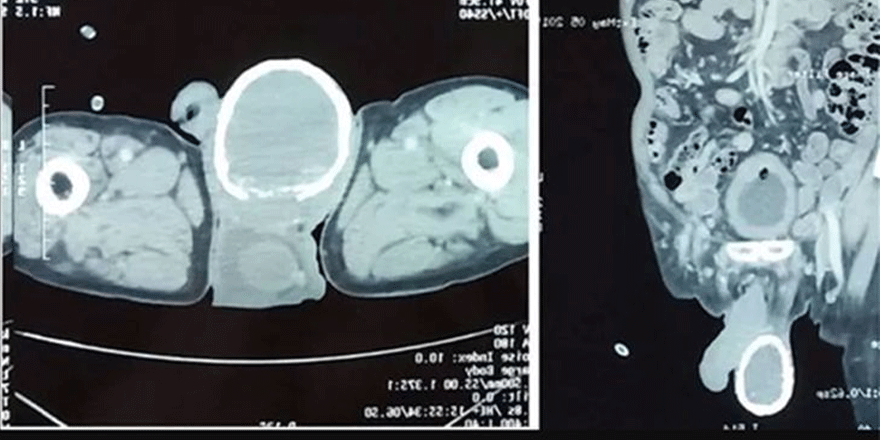

İdrar yolu enfeksiyonu belirtilerini yaşayan hastaya doktorlar gerekli birkaç test istediler ancak yaptıkları muayene sonucunda adamın bir testisinin kireçlendiği ve yummurta kabuğu şeklini aldığı görüldü.

Elle muyenede ise adamın bir testisinin taş gibi sertleştiği ortaya çıktı. Doktor bunun sivrisinek larvalarından kaynaklandığını adamın muhtemelen bir sivrisinek tarafından ısırıldığını öne sürdü.